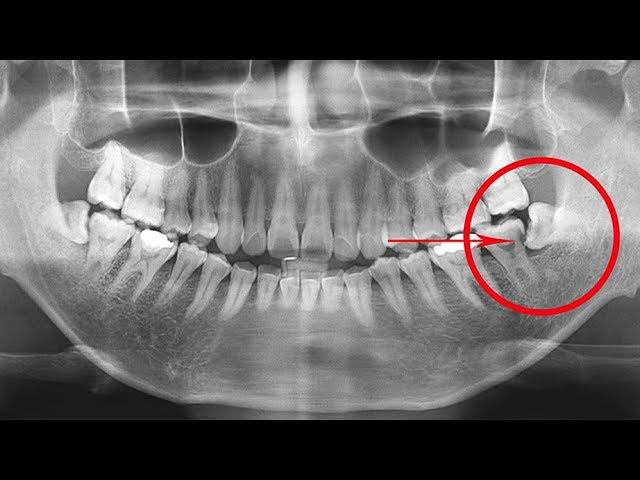

Как вы уже, наверное, догадались, строение зубов человека — результат длительной эволюции. Зуб любого живого существа «оптимизирован» под ту или иную пищу. Эта особенность позволяет тем же млекопитающим выживать почти что в любой точке планеты. Подготовлено DeeAFilm Studio http://vk.com/deeafilm_studio https://www.facebook.com/deeafilm/ !ПЛЮШКИН ДОМ! https://goo.gl/xH1Wpm Канал с короткометражками: https://goo.gl/uSvIhB Подписаться http://www.youtube.com/c/DeeAFilmStudio _________________________________________________________________ Чтобы заказать перевод/озвучку, пишите: deeafilm.studio@gmail.com или https://vk.com/mikhail_polezhaev Поддержать проект: Яндекс: 410012812221513 WebMoney: R134699928939